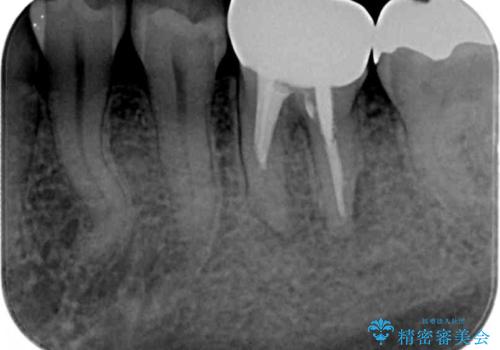

歯ぐきと銀歯の間に大きな凹みがあり、食べ物が詰まりやすく、また虫歯にもなりやすい状況です。

不十分な根管治療も精密根管再治療を行ったのち、精度の高いジルコニアセラミッククラウンで食べ物の詰まらない歯の形態へと改善していきます。